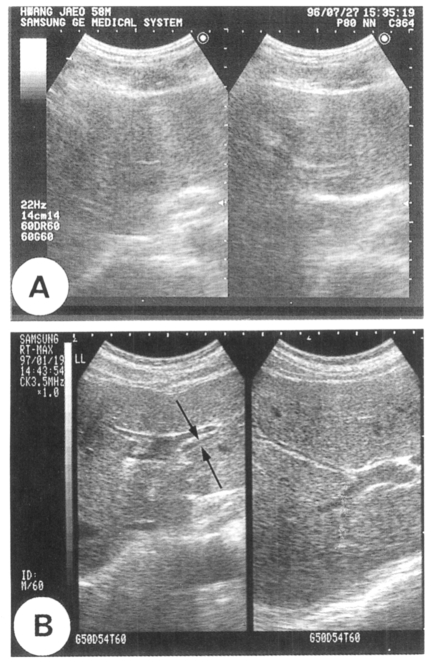

As presented in Figure 1, the sonography which showed the peripheral intrahepatic ducts was regarded as positive. On this basis, 61 (49.6%) of 123 residents, who were included more than once by both fecal examination and sonography in Koesan-gun village, were sonography-positive. Of the 123 residents, 23 were egg-positive and 100 were egg-negative. Twelve of 23 egg-positive cases (sensitivity, 52.2%) were sonography-positive and 51 of 100 egg-negative cases (specificity, 51%) were sonography-negative (Table 3).

Fig. 1

Sonographic images of the liver. A. A normal resident with negative findings. B. An infected resident showing the intrahepatic bile duct (arrows).